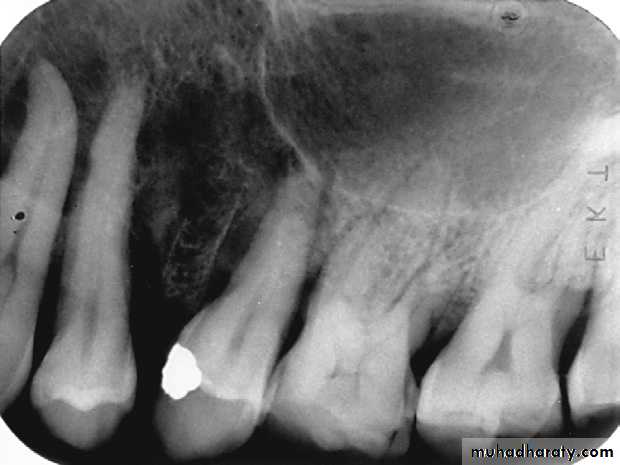

Defective Restorations

Amalgam overhang on the mesial surface of the mandibular first molar.

Ill-fitting restorations and open contacts between teeth contributing to the periodontal condition